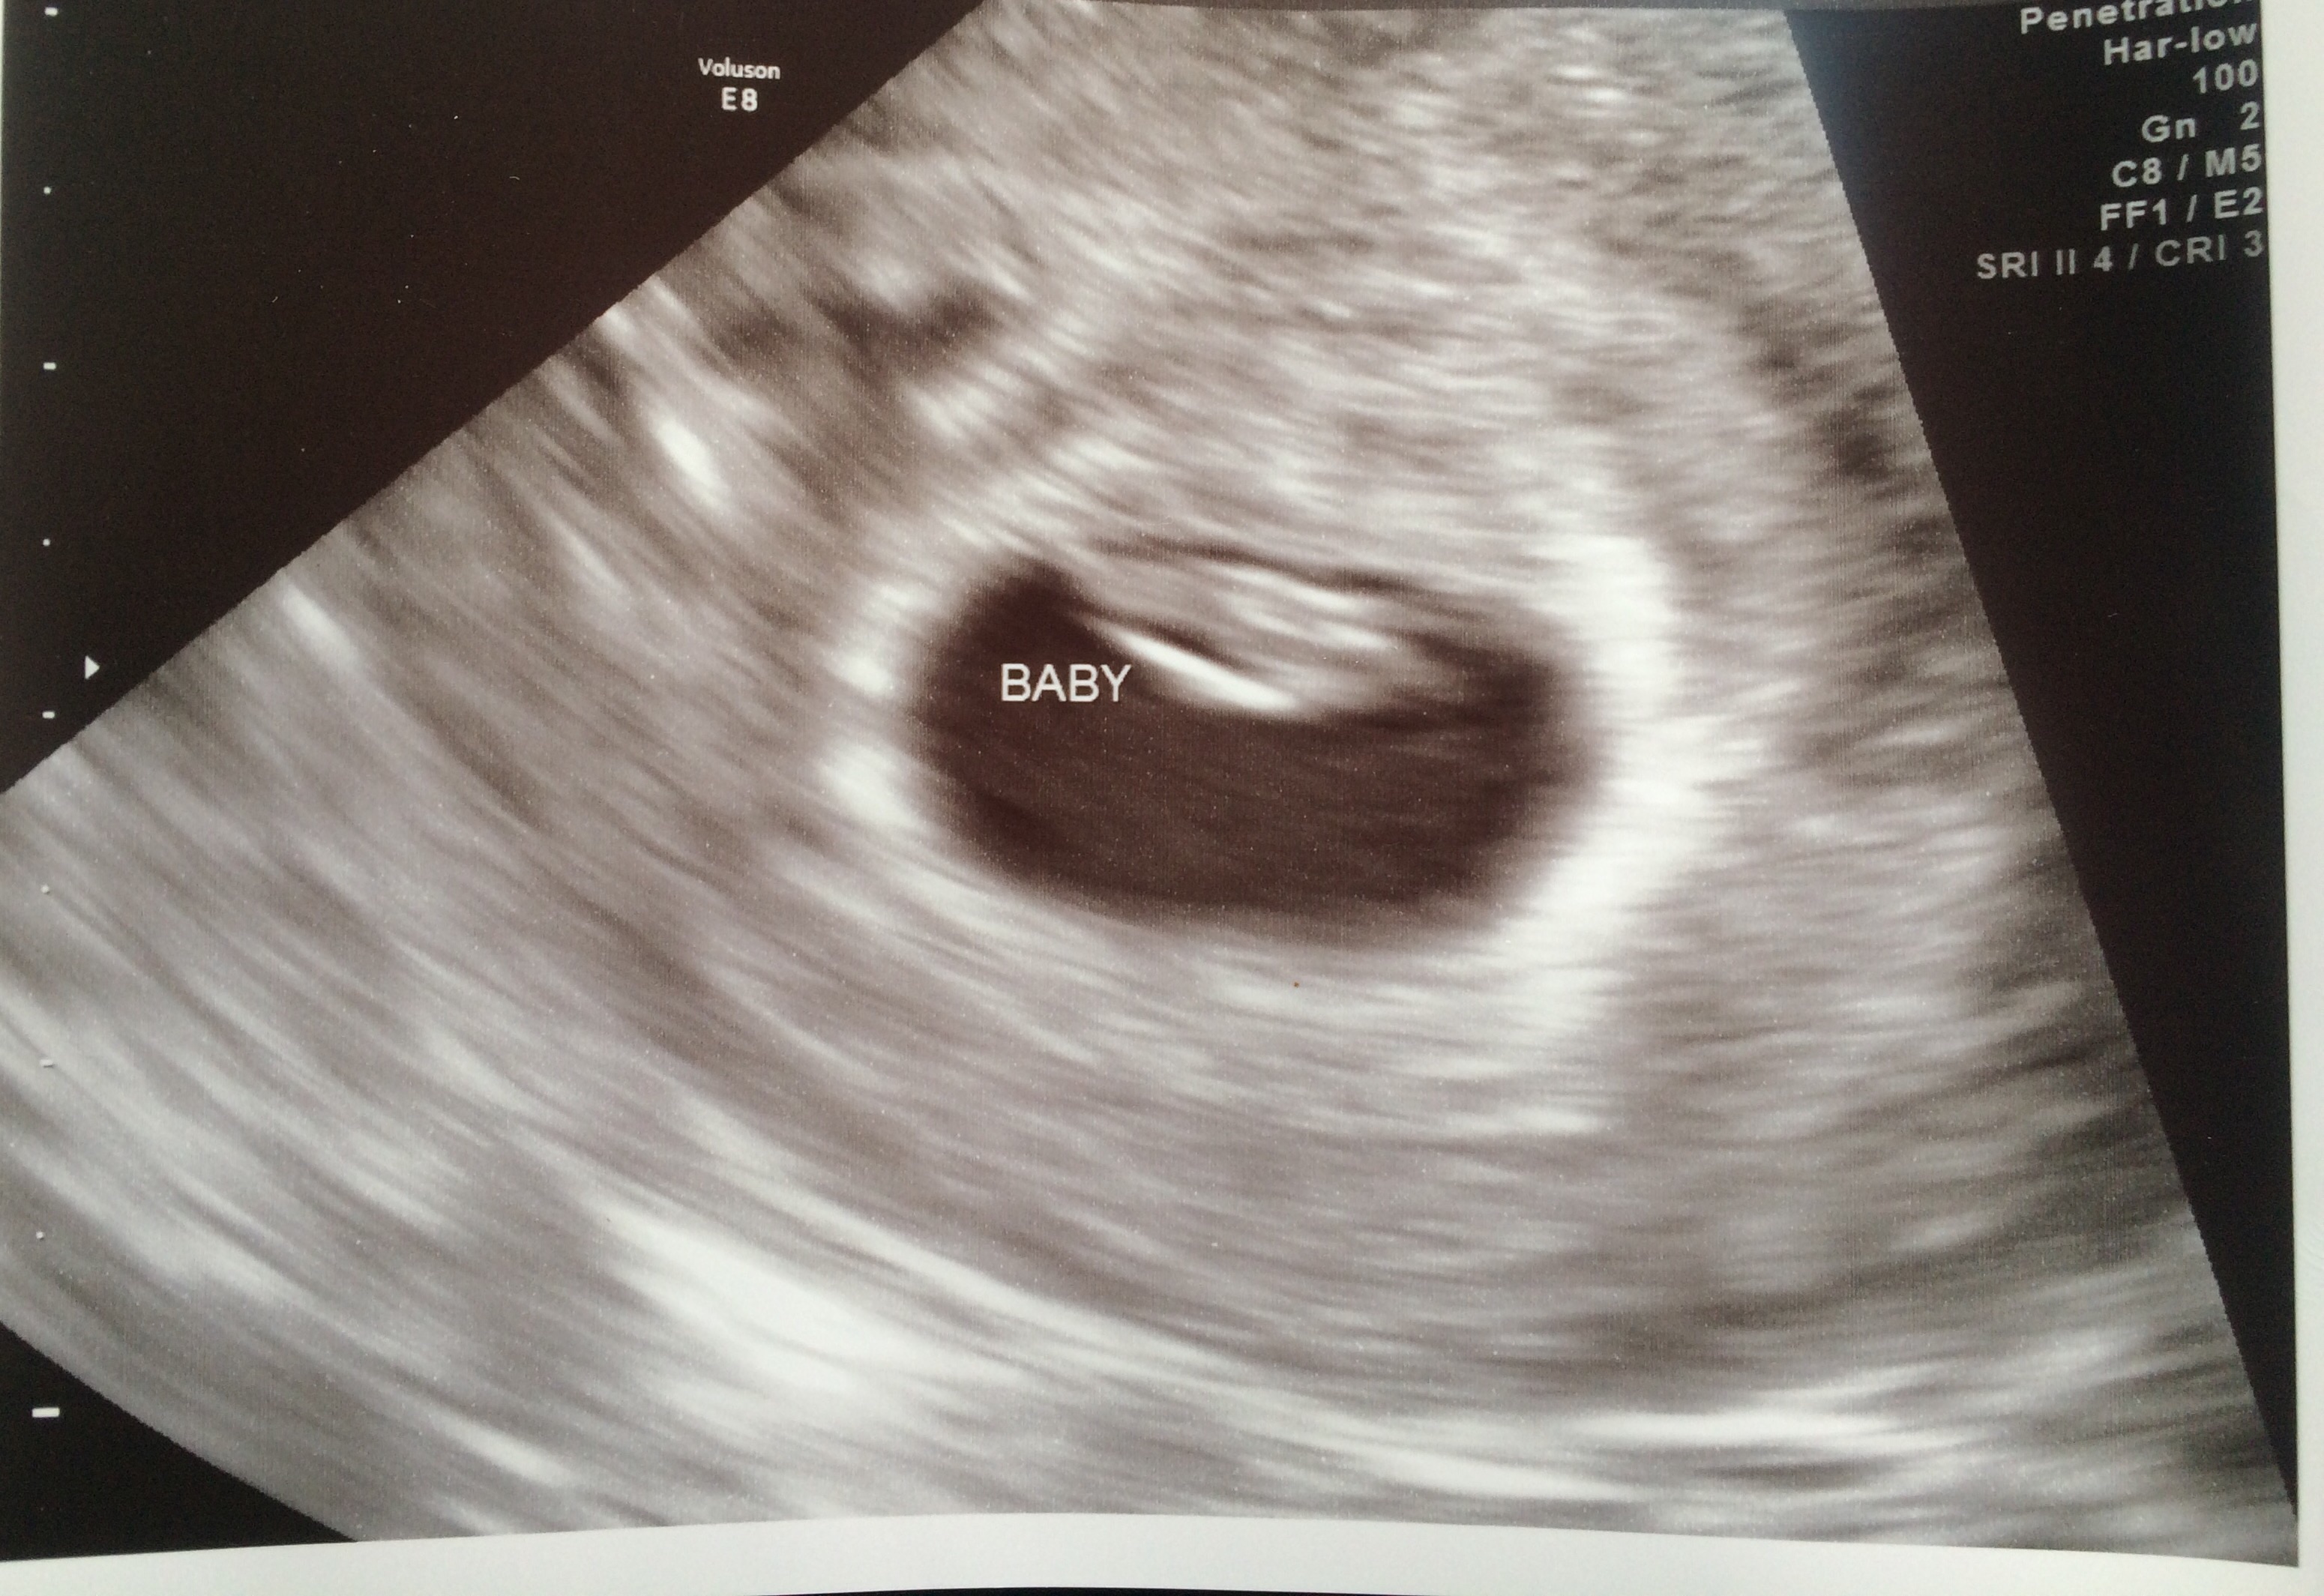

this was 7w1d I am 8w now.  I ran around waving it and telling people, "look!  Look what's in my uterus because I had sex!"  Toby said I was weird and needed to tone it down to "I am pregnant, would you like to see the u/s?" lmao  I word things oddly.